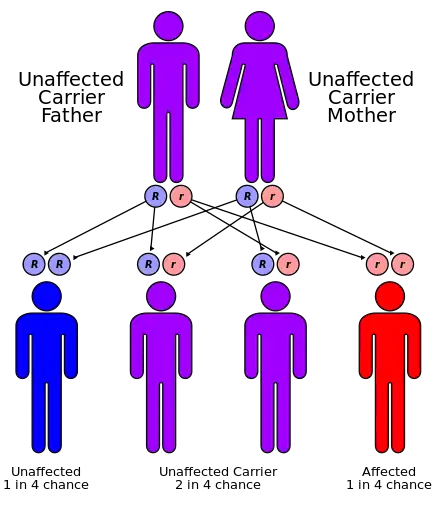

| Cystinosis has an autosomal recessive pattern of inheritance. | |

All forms of cystinosis (nephropathic, juvenile and ocular) are autosomal recessive, which means that the trait is located on an autosomal gene, and an individual who inherits two copies of the gene – one from both parents – will have the disorder. There is a 25% risk of having a child with the disorder, when both parents are carriers of an autosomal recessive trait.